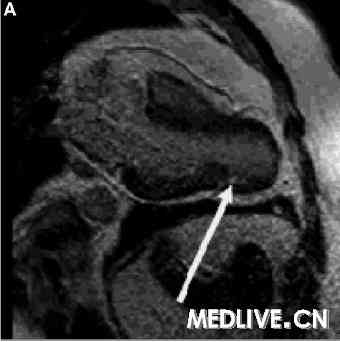

我们用一个带6个元件相控阵列线圈的1.5T的MRI扫描器。通过使用一种稳态梯度回波技术获取标准视图的电影回放,实施标准的心室功能检查。在心脏轴位和短轴平面用屏住呼吸的T1加权快速自旋回波MRI检查心脏和心包形态,并且在静脉给予钆对比剂后10分钟获取对比增强图像。MRI显示心尖处的心包缺如以及双心室尖部疝(图2和3),这些发现引导我们(将该患者)诊断为部分性CAP,LAD中部远端狭窄通过心包环来解释。用MRI完全确定CAP,用心室尖部疝解释LAD受压,以及已被证明的缺血导致了外科干预(图4A和4B)。在左乳内动脉成功地实施了心包成形术联合LAD旁路。术后即时MRI显示与心包成形术相关的心尖部运动明显改善。对照冠状动脉造影显示左乳内动脉通透性良好,LAD变形部分消失(图5)。该患者经过1年随访后目前没有(发生不良)事件。

图3A. 晚期增强显示心包环上的心肌内纤维化 |